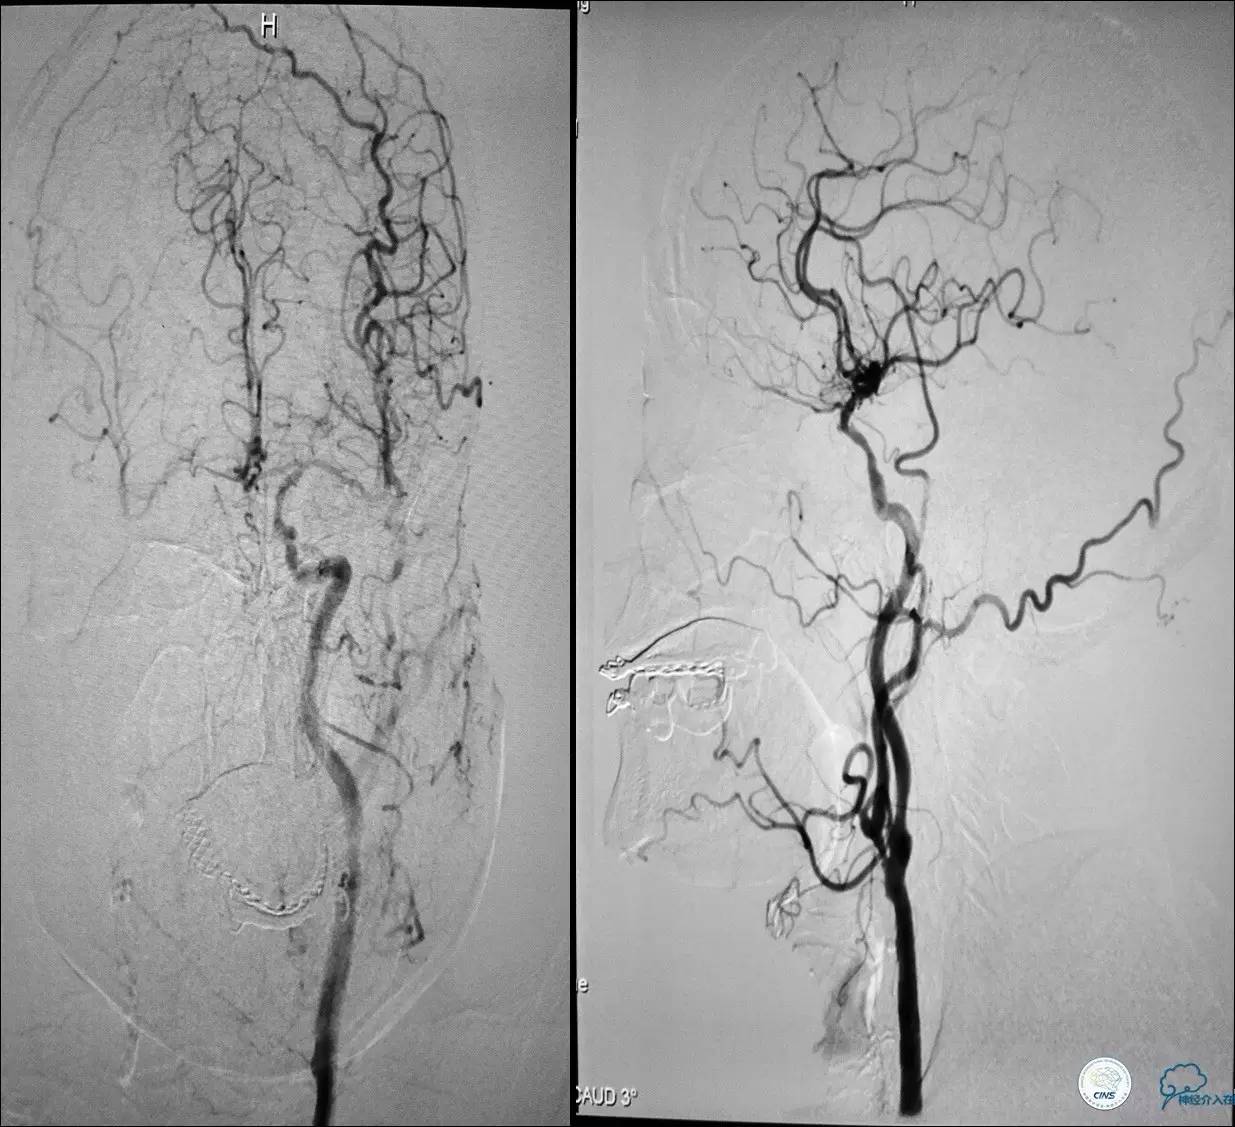

》男,70岁。

》主诉:阵发性头晕伴视物模糊两月余。

》查体:右侧肌力V-级。

》既往史:高血压,糖尿病。

》辅助检查:颈动脉B超显示:左侧颈内动脉起始部狭窄 90%,右侧颈内动脉起始部80%。